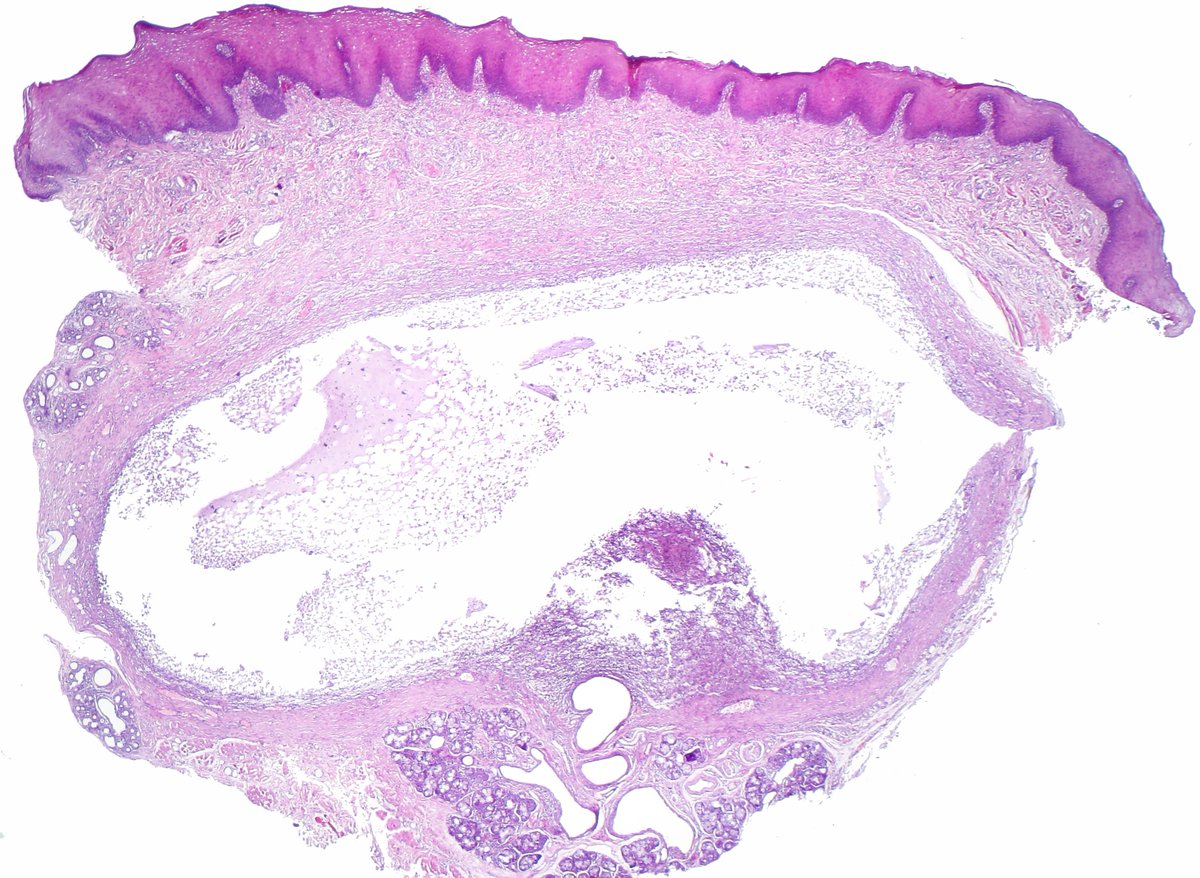

Atypical carcinoid of the lung exhibiting endobronchial growth, increased mitotic activity was seen (2-10 per 10 HPF). #pathology #PulmPath